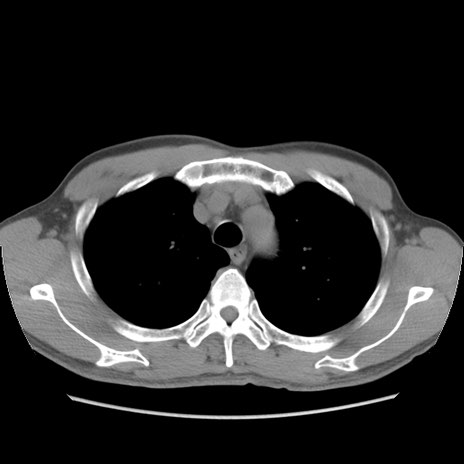

症例56 CT(横断像)

脂肪ウインドウ